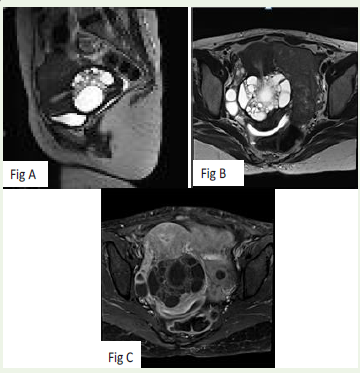

Figure 2: A and B: sagittal and axial T2 showing increase in size

multiloculated cystic lesion.

C – post contrast axial images showing interval increase in thickness of

septa.

Three years later, she re-presented with profuse mucinous vaginal

discharge. Local examination again revealed a bulky cervix, and repeat

MRI was performed for reassessment [Figure 2]. Compared with the

initial MRI, there was mild further enlargement of the lesion with

stromal expansion. Post-contrast imaging showed a minimal increase

in wall thickness, but no definite solid component was identified.

There was no evidence of parametrial extension, pelvic, or inguinal

lymphadenopathy. In view of the progressive nature of the lesion and

persistent symptoms, adenoma malignum was strongly suspected,

and the patient consented to surgery.